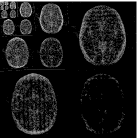

Baseline 5 months 10 months 20 months 23 months

While the scenario of longitudinal studies is fundamentally different from dynamic MRI in many aspects, we still find that similarity across time points exists in many cases. Figure 1 shows an example of the same axial slice taken from multiple scans acquired from a patient with Optic Pathway Glioma (OPG), demonstrating a relatively slow growing tumor pattern. The bottom row of the figure shows the representation of each time point in Daubechies-4 wavelet transform (Daubechies et al., 1992), which is widely used as a sparse transform for brain MRI. The similarity between image slices acquired at several time points is clearly demonstrated. Moreover, the representation of the images in the wavelet domain is sparse, and the locations of the dominant wavelet coefficients (a.k.a the support of the image in the wavelet domain) are similar across the patient’s time points.